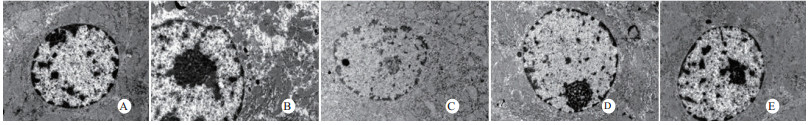

扫描电镜下可见,假手术组肺泡形态完整,肺泡壁光滑;感染性休克组肺泡明显压缩畸形,肺泡隔肿胀、扭曲、隆起;U50488H+感染性休克组肺泡形态大致完整,少数肺泡壁肿胀受损(图 5)。透射电镜下可见,假手术组心肌细胞形态正常;感染性休克组心肌细胞溶解、坏死、肌纤维断裂;U50488H+感染性休克组心肌细胞大致正常,无明显坏死(图 6)。假手术组肝细胞形态正常,毛细胆管未见扩张;感染性休克组肝细胞大片坏死,毛细胆管明显扩张;U50488H+感染性休克组肝细胞形态大致正常,毛细胆管略扩张(图 7)。假手术组肾小管上皮细胞形态狭长,核卵圆形,位于基底部;感染性休克组肾小管上皮断裂,微绒毛缺失;U50488H+感染性休克组肾小管上皮细胞大致正常,微绒毛不平滑,但无明显坏死(图 8)。

| A:假手术组,B:感染性休克组,C:U50488H+感染性休克组,D:nor-BNI+U50488H+感染性休克组,E:nor-BNI+感染性休克组 图 7 肝细胞透射电镜检查(×10 000) Fig 7 Transmission electronic microscopic photos of liver(×10 000) |

| A:假手术组,B:感染性休克组,C:U50488H+感染性休克组,D:nor-BNI+U50488H+感染性休克组,E:nor-BNI+感染性休克组 图 8 肾组织透射电镜检查(×15 000) Fig 8 Transmission electronic microscopic photos of kidney(×15 000) |

本研究还进一步观察了感染性休克大鼠重要脏器的病理学变化与超微结构。结果发现,感染性休克时,肺泡壁破坏严重,血管壁和肺泡间隔明显增厚,炎症细胞浸润较多,肺泡明显压缩畸形,肺泡隔肿胀,扭曲,隆起。该结果与潘景业等的报道一致。同时实验发现,U50488H可减轻感染性休克肺泡壁出血水肿与肺组织炎性细胞浸润,抑制肺间隔增厚。实验还观察到感染性休克大鼠心肌纤维肿胀、扭曲、断裂、溶解,并由此导致心功能障碍。U50488H亦可减轻线粒体肿胀崩解和心肌细胞溶解与坏死,可能与U50488H减轻心肌抑制有关[12],具体机制与分子通路尚需进一步实验验证。本研究还观察到感染性休克大鼠肝细胞出现肿胀、空泡样脂肪变性和点状/小片状坏死,毛细胆管明显增多、扩张;肾小管细胞轻度水肿、空泡变性,肾小管上皮细胞微绒毛缺失,细胞崩解,肾小管上皮断裂。预先给予U50488H可显著减轻感染性休克肝细胞浊肿、肝血窦扩张和炎性细胞浸润;抑制肾小管上皮细胞核变形、微绒毛坏死和间质出血水肿。nor-BNI可阻断这一效应。上述结果均提示U50488H可通过激动κ-阿片受体,改善肝脏和肾脏血流量保护感染性休克肝脏和肾脏功能,具体机制可能和细胞凋亡等相关。